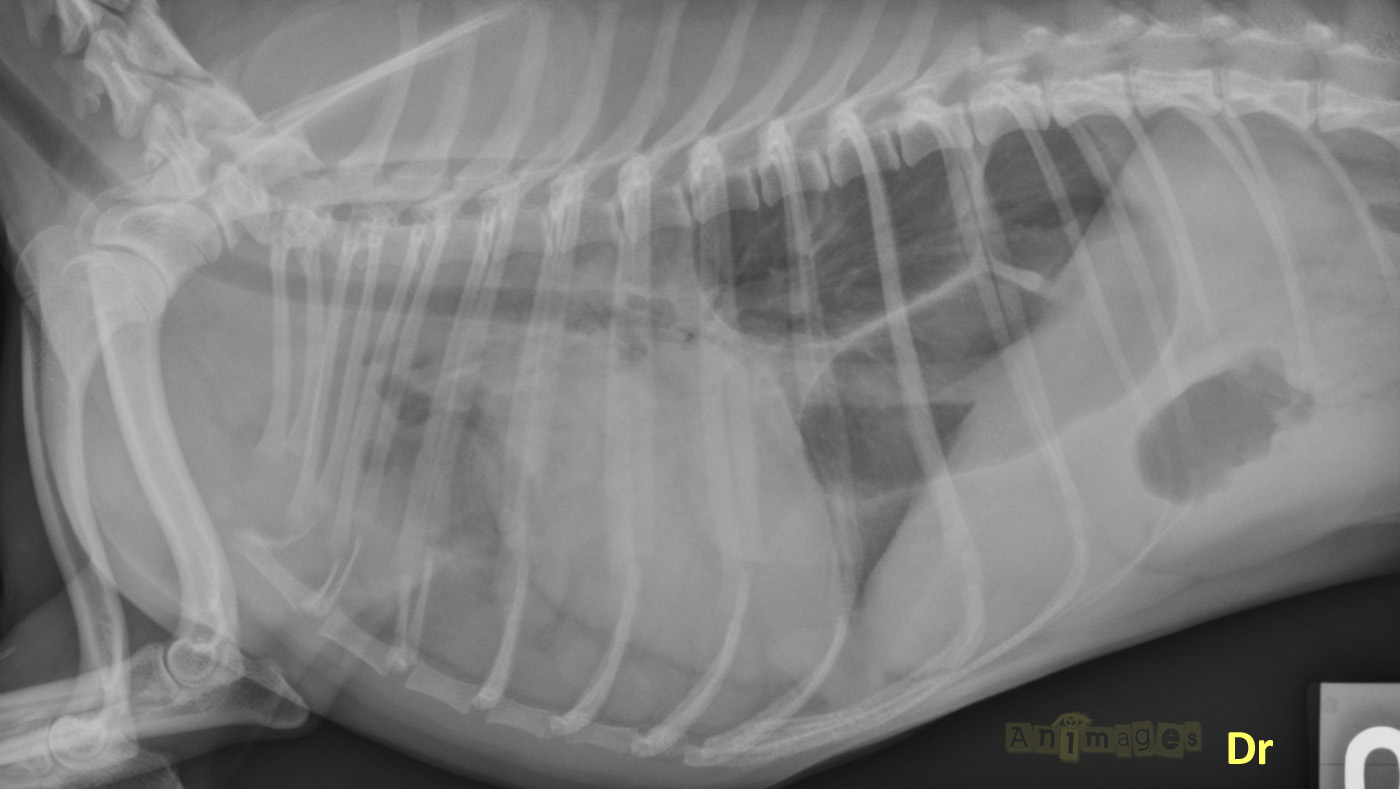

148595_lat